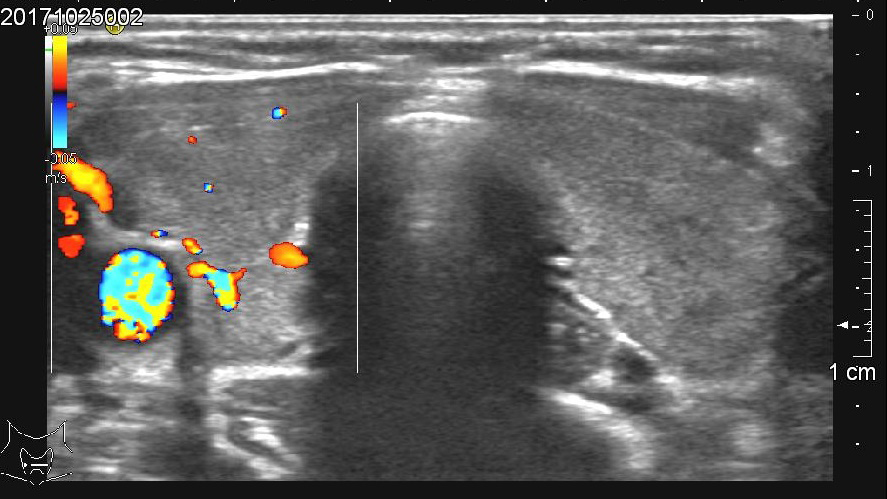

- Mit dem Ultraschallgerät lassen sich einerseits Größe und Volumen der Schilddrüse bestimmen, andererseits lassen sich auf dem Schwarzweiß-Bild bereits mögliche Knoten oder Zysten erkennen. Die farbcodierte Doppler-Sonographie kann die Durchblutung der Drüse darstellen und so Hinweise auf mögliche Erkrankungen geben.